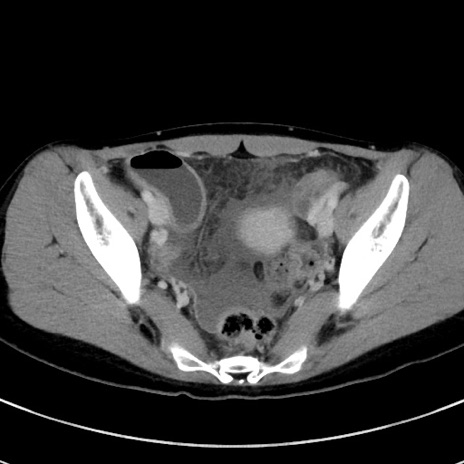

冠状断像

【症例】20歳代女性

【主訴】嘔吐、下腹部痛

【現病歴】昨日夕食後に嘔吐し下腹部痛が出現。本日になっても嘔吐持続し改善しないため来院。

【身体所見】意識清明、BT 37.2℃、BP 108/67mmHg、腹部:平坦、やや硬、下腹部正中から右にかけて圧痛あり、反跳痛軽度あり、tapping pain(+)。

【データ】WBC 13600、CRP 14.94